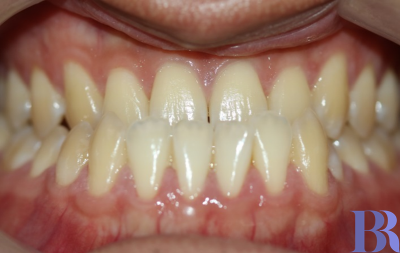

초진 입안사진입니다

치아가 거꾸로 물리고 있으나

실제 골격이 나온것에 비해서는

덜 나와 보이네요.

양악수술 대상자의 전형적인

치아 상태를 볼수 있습니다.

치성보상작용으로 인해

실제 골격에 비해 치아 간격이

좁아 보입니다

아랫니와 윗니 앞뒤 차이가

외모에 비해 심하지는 않습니다